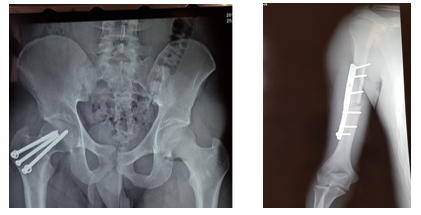

FRACTURA DE CADERA Y HÚMERO DERECHO